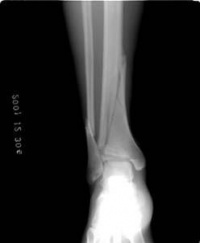

x线检查在胫腓骨骨折中用于诊断、估计骨折愈合的程度、发现骨折的并发症及、做必要的鉴别诊断。

在临床上,一旦怀疑有胫腓骨骨折,就要拍摄小腿正侧位的X线片,照片质量要求较高,除了能发现明显骨折外,对怀疑的线状裂纹也要确定,因为线状骨折也影响愈后和治疗,如行内固定,其稳定性要把线状骨折的因素考虑在内。

在晚期估计其愈合的程度时,有时要拍摄透过骨折端的斜位片。复位后的x线片最好包括膝、踝两个关节,以确定这两个关节轴线在平行的位置,防止晚期因膝、踝关节面的不平行而造成的并发症。原则上拍小腿x线片时要包括胫腓骨的全长。以防止低位胫骨骨折,合并有高位的腓骨骨折发生漏诊。

在骨的x线描述上,首先确定骨折的部位,在上l/3、中l/3或下1/3。再确定骨折类型是横断、斜行或螺旋型骨折,骨折有无粉碎,以及是否多段。侧方移位严重则愈合很难。×线片上不易确定上下骨折段的旋转移位,要从临床上来判断和纠正。

X线正位片应包括胫腓骨全长,以免漏诊。X线可见骨折线、碎骨片、断端移位等。